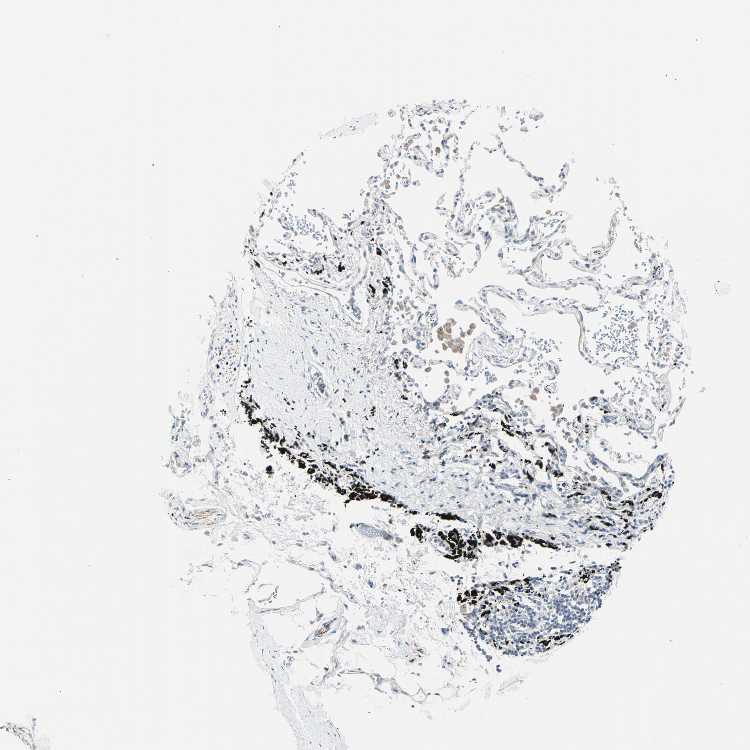

ADIPOSE TISSUE - Antibody stainingi

Antibody staining in the annotated cell types in the current human tissue is reported as not detected, low, medium, or high, based on conventional immunohistochemistry profiling in selected tissues. This score is based on the combination of the staining intensity and fraction of stained cells.

Each image is clickable and will lead to virtual microscopy that enables deeper exploration of all samples and also displays staining intensity scores, fraction scores and subcellular localization as well as patient and tissue information for each sample.

Antibody HPA061615Antibody CAB007786

Adipocytes Not detectedNot detected